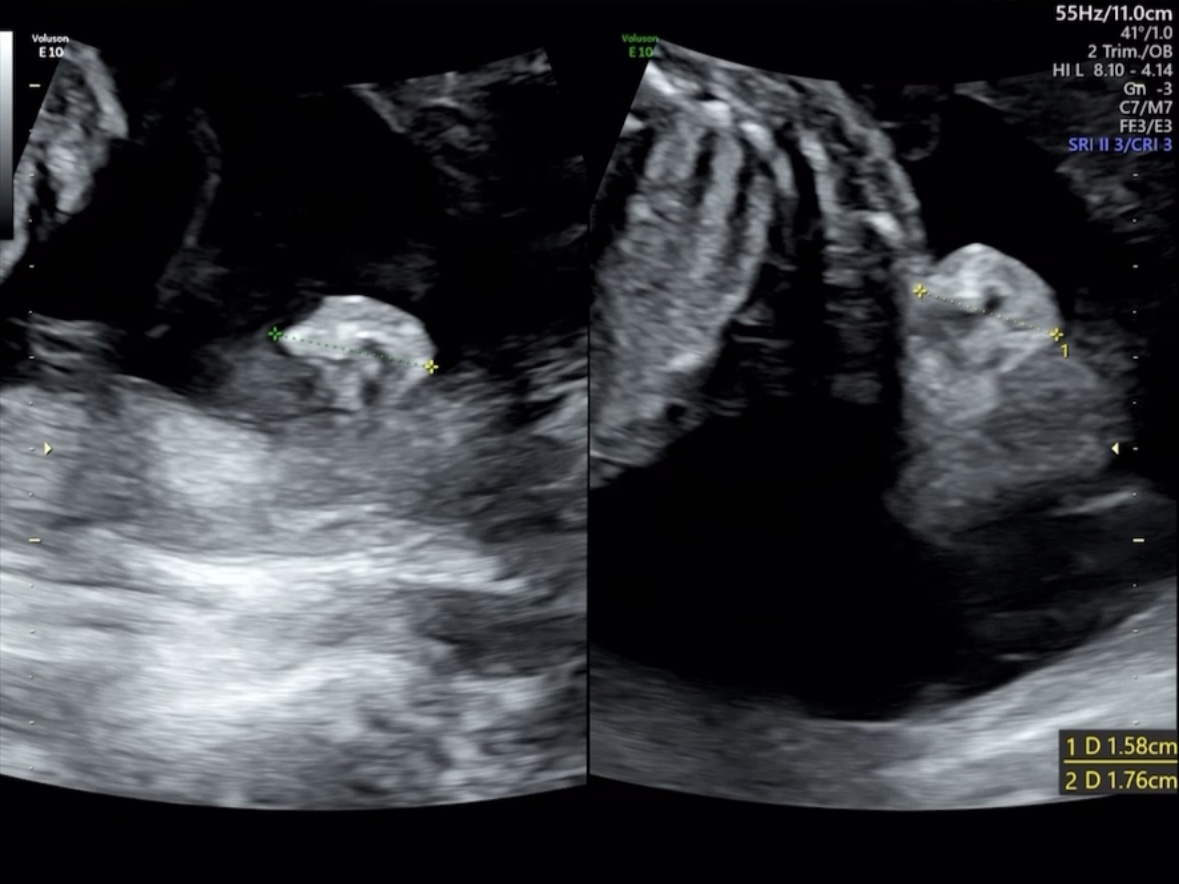

추후 검진이 필요했던 콩팥

다른 장기들은 정상범위에 있었지만, 주수 대비 콩팥이 늘어나 있엇다(현재: 5.51mm, 21주 정상범위: 4mm 이하).

콩팥과 관련이 있는 양수량(13.51cm)은 다행히도 정상범위라 이상이 있어 보이지는 않지만 한달후에 다시 살펴보자고 하셨다.

한달 후 재초음파(25주)

다행히도, 한달 후 콩팥을 초음파 상으로 다시 봤을때는 2.27mm로 정상범위로 돌아와 있었고, 의사 선생님께서 이상이 있어서 커진건 아닌것 같다고 하셨다. 마음이 놓였다.